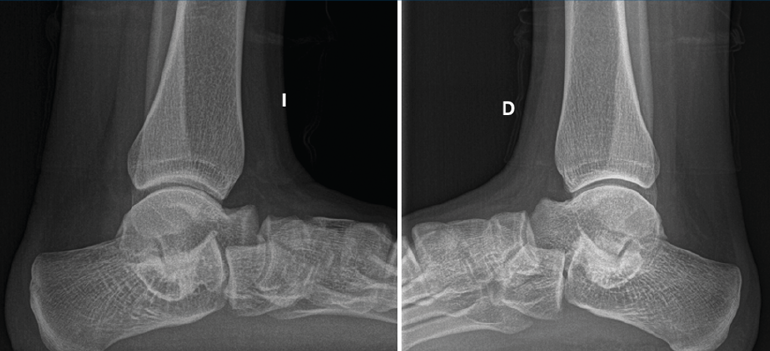

Segundo caso (Figura 7)

Se trata de una paciente mujer de 18 años de edad, higienista dental, sin antecedentes patológicos de interés, que presenta pies planos valgos bilaterales dolorosos, el derecho de 23° y el izquierdo de 21° de valgo, por sinostosis calcaneoastragalina media en ambos pies. En ella observamos básicamente una clínica de dolor en el seno del tarso, con déficit de movilidad de la articulación subtalar en ambos pies. Se realiza estudio mediante radiografías de los pies y los tobillos en carga y TAC de ambos pies (afectación bilateral). Radiológicamente, las articulaciones tibioperoneoastragalina y subtalar están preservadas. Se diagnostica de coalición tarsal de tipo 4 de la clasificación de Rozansky(26). El balance articular es de: flexión = 45°; extensión = 20°; inversión = 0°; eversión = 0°. La escala de la AOFAS para el tobillo derecho presentaba una puntuación de 62 (20-37-5). Los ángulos radiológicos iniciales son: Moreau-Costa-Bartani interno = 141°; declinación talar = 18,4°; Meary = 6,3°; Kite = 25,6°; taloescafoideo = 48,3°.

Figura 7. Radiografía del segundo caso: sinostosis talocalcánea media en ambos pies.